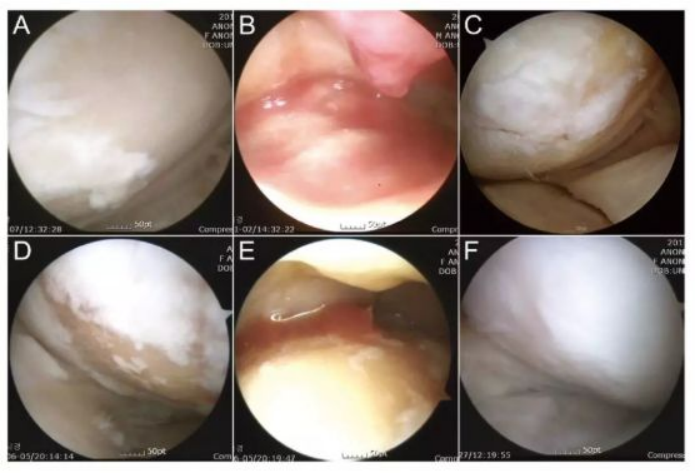

下图a为治疗前关节镜检查结果,,,可以看出软骨存在缺损。。图b为脂肪间充质干细胞联合PRP治疗,,,,图c为治疗后结果,,,通过间充质干细胞治疗,,,软骨得到了修复。。。

下图中A-C为51岁男性膝关节镜,,,D-F为54岁女性膝关节镜。。。A/D为治疗前,,白色示意软骨,,浅黄色示意裸露的骨。。。。B/E为间充质干细胞注射。。。C/F为治疗后的关节镜检查。。。。